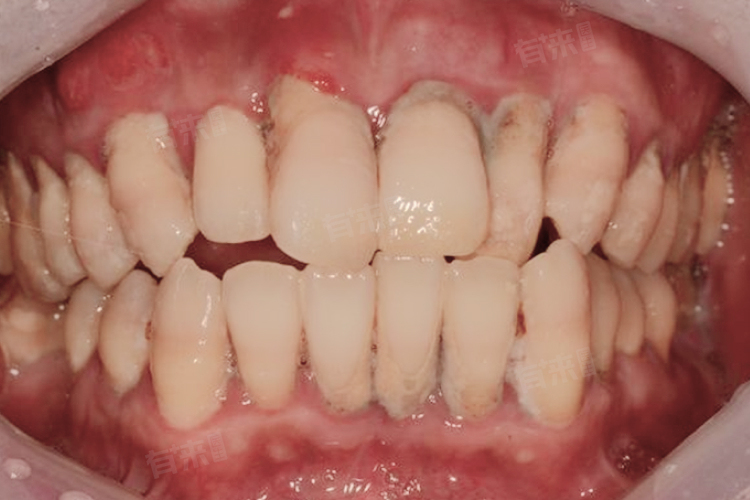

2、影响牙周组织:牙结石长期堆积在牙周,会引发牙周炎。牙周组织遭到破坏,牙槽骨逐渐吸收,牙周袋形成。随着病情发展,牙齿会逐渐松动移位,甚至脱落。牙周炎发展到晚期,治疗难度极大,所以发现牙结石应及时处理,预防牙周炎发生。

4、导致牙齿松动:随着牙结石的持续积累和牙周组织的破坏,牙齿的支持结构逐渐减弱,牙齿失去足够支撑,就会开始松动。牙齿松动不仅影响咀嚼功能,还会进一步加重牙周组织负担,形成恶性循环,因此必须重视牙结石问题,避免牙齿松动。